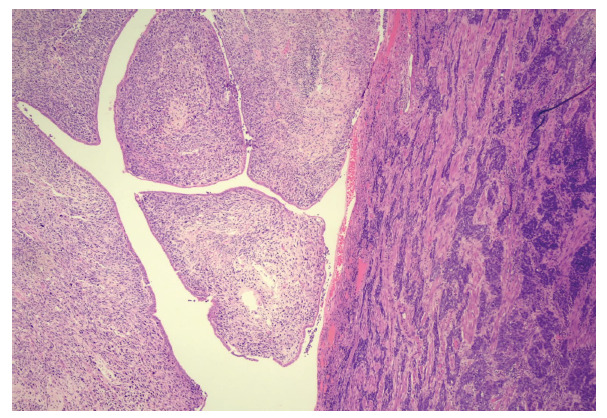

Material and methods: A 76-year-old patient who presented to the national cancer referral center in Bogota (Colombia), where she was diagnosed with a uterine collision tumor consisting of a seroustype endometrial adenocarcinoma and a cervical adenosarcoma. The patient underwent surgical treatment followed by chemotherapy and supplemental radiotherapy, and died 16 months later. A search was conducted in the Medline via PubMed and Embase databases, including reports and case series of women with a diagnosis of uterine collision tumor, with retrieval of information regarding diagnosis, treatment and prognosis. A narrative summary of the findings was made.